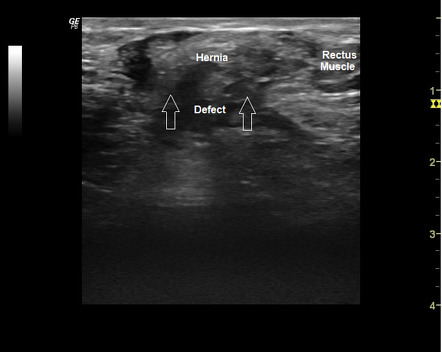

В режиме В-сканирования визуализируется дефект апоневроза передней брюшной стенки с пролабированием внутрибрюшного содержимого, что указывает на наличие грыжевого мешка в зоне послеоперационного рубца.

В режиме высокого пространственного разрешения определяется структура грыжевого содержимого — участки сальника, кишечной петли или жидкостных включений, при этом визуализируются границы и толщина грыжевых ворот.

В режиме с линейным высокочастотным датчиком определяется толщина рубцово изменённых тканей, окружающих грыжевой дефект, что позволяет оценить степень фиброза и анатомические особенности грыжевых ворот.